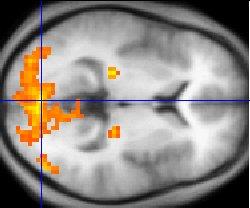

נוסף על השינויים הביוכימיים שנמדדו בגוף בעקבות מדיטציה, מחקרי דימות (סריקות מוחיות) מצאו גם שינויים מבניים ותפקודיים במוח. נמצאה למשל עלייה בנפח ובצפיפות של החומר האפור (החומר שבונה את גופי תאי העצב) באזורים שמעורבים בביצוע מטלות חשיבתיות קוגניטיביות ובקשב, כגון ההיפוקמפוס, הסטריאטום וחלקים מבקליפת המוח. גם עוביה של קליפת המוח גדל בעקבות מדיטציה.

באזורים של קליפת המוח שקשורים לקשב, למודעות ולעיבוד רגשי נצפתה בעקבות המדיטציה עלייה בפעילות שלהם. באופן לא מפתיע נמצא גם שיפור במגוון של מטלות חשיבתיות שביצוען קשור לאזורים הללו.

תמונת דימות תהודה מגנטית תפקודי (fMRI) של המוח. האזורים הכתומים והצהובים מציינים פעילות מוחית מוגברת | צילום: ויקיפדיה